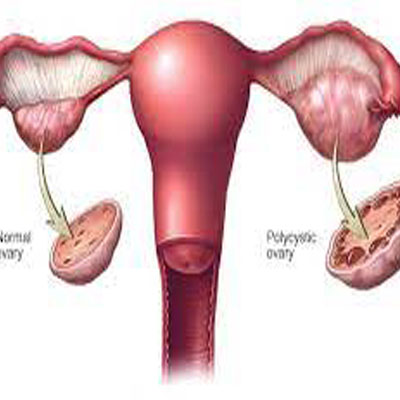

Diseases Treated

Spinal Problems Digestion Diseases Joints & Bones Problems Neurological Diseases Cardiovascular Disorders Respiratory Diseases Thyroid Problems Skin Diseases Diabetes Kidney Problems Male Reproductive Diseases Gyanecological Problems Opthalmic (Eyes) Problems Auto Immune Diseases Children Problems Hair Problems Addiction Rehabilation of Accidential Cases

Stress Management Detoxification Rejuvenation Relaxation Immunity Enhancement Annual Wellness Health Package Senior Citizen Health Package Lifestyle Disease Management Essence of Ayurveda Pain Management Package Strength & Weight Gain Hair Care Skin & Beauty Care Gentleman Health Care Package Womens Health Care Package Kids Health Care Package Deaddiction Program Anti Ageing Program